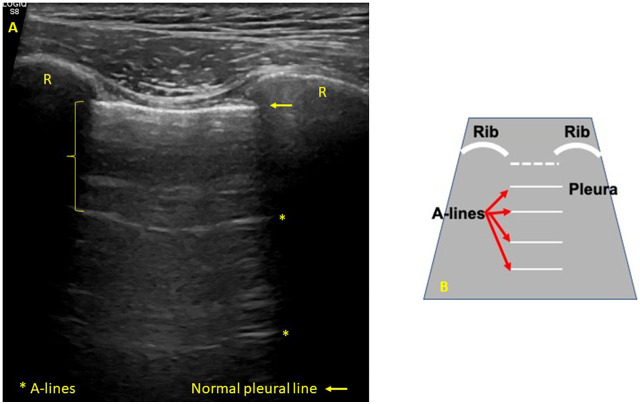

The interpretation of lung ultrasound is the result of the analysis of artifacts rather than exact representations of anatomical structures, which appear when changes in the physical properties of the lung occur. Its application to the study of interstitial lung disease (ILD) associated with autoimmune diseases has aroused great interest in the last 10 years, as evidenced by a growing number of publications studying its usefulness in the diagnostic process, as a prognostic marker and as an aid in monitoring of patients. The main elements in lung ultrasound interpretation in ILD are the B lines and the changes in the pleural line. B lines are vertical artifacts that are generated when there is a partial decrease in the air content of the lung parenchyma and/or the volume of the interstitial area expands. Pleural line alterations that can be seen are irregularities, thickening, fragmentation, or subpleural nodules. Both the B lines and the changes in the pleural line have shown a significant positive correlation with the evidence on chest computed tomography [high resolution computed tomography (HRCT)] of ILD associated with autoimmune diseases, with sensitivity and negative predictive values of up to 100%. These results, together with the safety, accessibility, and low cost of lung ultrasound, support this imaging technique as a promising screening method for optimizing the indication for HRCT. The role of lung ultrasound regarding sensitivity to change needs further investigation with multicenter prospective studies.